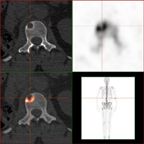

Sodium fluoride PET/CT Scan of a bone metastasis of kidney cancer; the PET scan shows the metabolic reaction of the bone